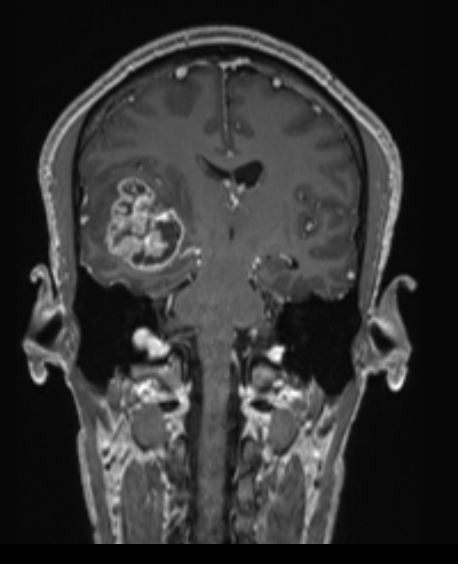

Χωροκατακτητική Εξεργασία δεξιού Κροταφικού Λοβού